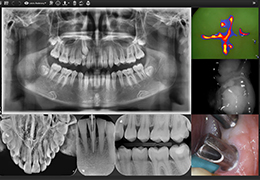

ANYTHINK 经导管主动脉瓣膜置换术分析系统